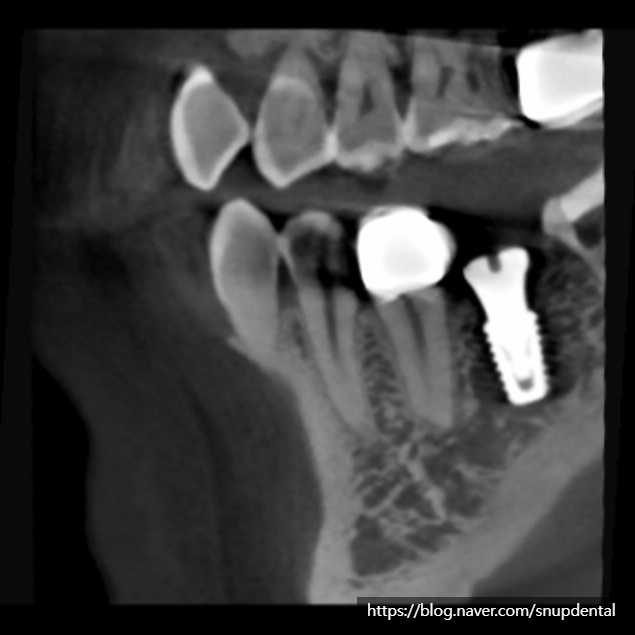

부분 CT를 촬영하여 현재 치조골 상태 확인 및 임플란트 수술 계획을 잡고

임플란트 수술 후 부분 CT 및 구강 내 사진